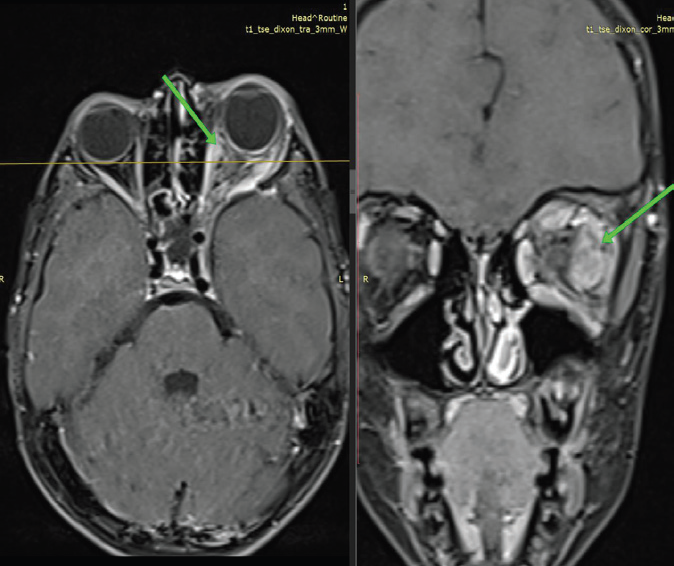

MRI of the brain and orbits with contrast demonstrated hypoplasia of the left sphenoid wing with herniation of brain parenchyma and CSF into the superior aspect of the left orbit, consistent with a left

Figure 1: MRI brain, axial T2-weighted image OF 39-YEAR-OLD

GENTLEMAN WITH KNOWN NF-1 demonstrates prominent arachnoid

spaces in the left anterior temporal region, secondary to the orbital

encephalocele. There is compression and medial deviation of the left optic

nerve without abnormal enhancement, excluding optic nerve glioma or optic

nerve sheath meningioma. There is severe narrowing of left superior orbital

fissure and compression of optic nerve at this level.

Figure 2: MRI brain, post contrast coronal T1 FS-weighted image OF

39-YEAR-OLD GENTLEMAN WITH KNOWN NF-1 demonstrates herniation

of brain parenchyma and cerebrospinal fluid into the superior aspect of the

left orbit, consistent with a left orbital encephalocele, resulting in left-sided

proptosis.

orbital encephalocele. This resulted in left-sided proptosis with

compression and mild medial deviation of the intraorbital segment

of the left optic nerve. Marked narrowing of the left superior orbital

fissure was noted, with optic nerve compression at this level.

Prominent arachnoid spaces were seen in the left anterior temporal region secondary to the encephalocele, with medial displacement of the left middle cerebral artery. No abnormal enlargement or postcontrast enhancement of the optic nerve was identified, effectively excluding optic nerve glioma and optic nerve sheath meningioma. Additional findings included multiple scalp neurofibromas and T2/FLAIR hyperintense foci involving the bilateral thalami and periventricular regions, consistent with focal areas of signal intensity (FASI). The left sphenoid sinus was hypoplastic.

CT of the skull base confirmed hypoplasia of the left sphenoid wing with loss of the normal bony separation between the middle cranial fossa and the orbit. Prior imaging studies had described the lesion as an arachnoid cyst, leading to delayed recognition of the underlying pathology.